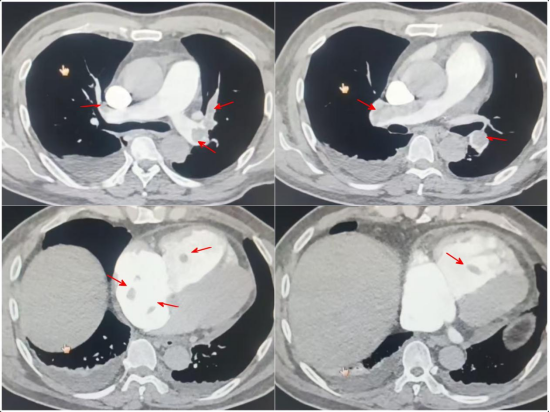

患者为54岁的中年男性,入院3周前无明显诱因出现胸闷、气短症状,在当地卫生所按“肺部炎症”治疗后效果不佳。入院4天前患者突发短暂晕厥,此后就诊于当地市医院,行下肢静脉超声提示“右下肢深静脉血栓形成”,肺动脉CTA提示“双肺动脉多发血栓形成”,更危险的是,心脏超声发现患者右心房、右心室内已形成多发活动性血栓,其中最大者达5.1*2.1cm,随心跳剧烈摆动,宛如一颗随时可能脱落、导致患者猝死的“心脏内炸弹”。当地医院紧急为其植入下腔静脉滤器防止深静脉血栓继续脱落导致更大面积的肺栓塞,并迅速转诊至我院。

经过紧张而充分准备,抢救手术连夜迅速展开。打开心包后,发现患者右房右室严重肿胀,中心静脉压达38mmHg,血压、氧饱和度高峰主任团队迅速建立体外循环,心脏停跳后切开右心房,探查仅发现右心房内少量血栓,而原心脏超声提示的右心房及右心室内大量血栓已脱落至肺动脉!随即切开肺动脉主干,取出大量新鲜及机化血栓,仔细探查肺叶及肺段分支动脉,尽量清理残留血栓,解除肺动脉血流的“路障”;术中还发现患者三尖瓣瓣环明显扩大,瓣膜重度返流,使用成形环进行了三尖瓣成形。手术过程有条不紊地顺利完成,但由于肺栓塞导致的继发肺动脉高压及右心功能障碍,心脏复跳后患者不出所料地出现右心功能不全,血氧饱和度下降等表现,手术团队当即按术前预案为患者施行了VA-ECMO辅助支持。